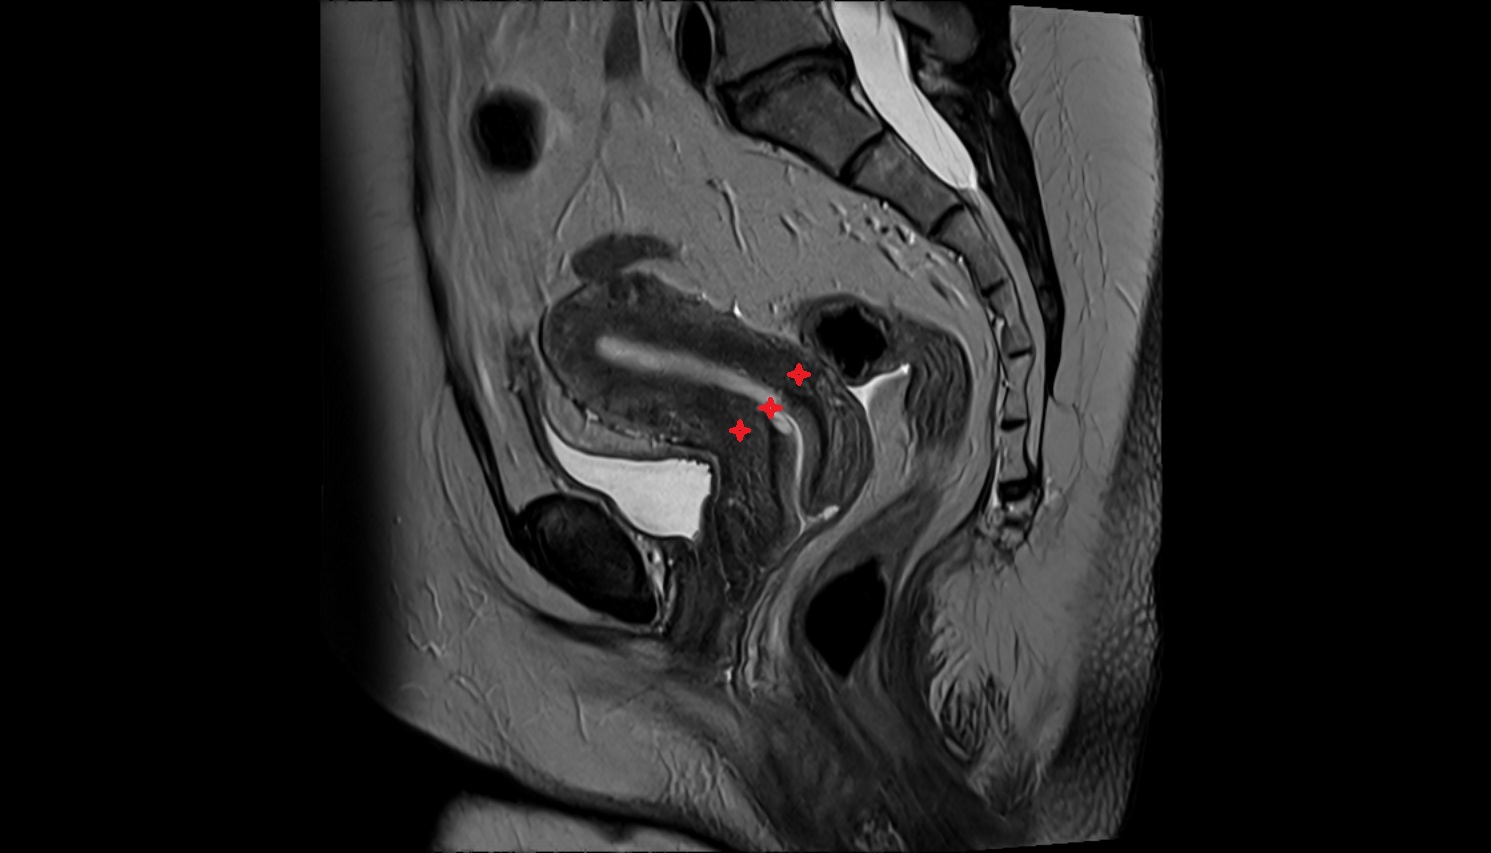

- Uterus

- Cervix of uterus

- Vagina

- Endometrium of uterus

- Myometrium of uterus

- Junctional zone of uterus

- Endocervical canal

- Internal os of the cervix

- External os of the cervix

- Vesicouterine pouch

- Rectouterine pouch (pouch of Douglas)